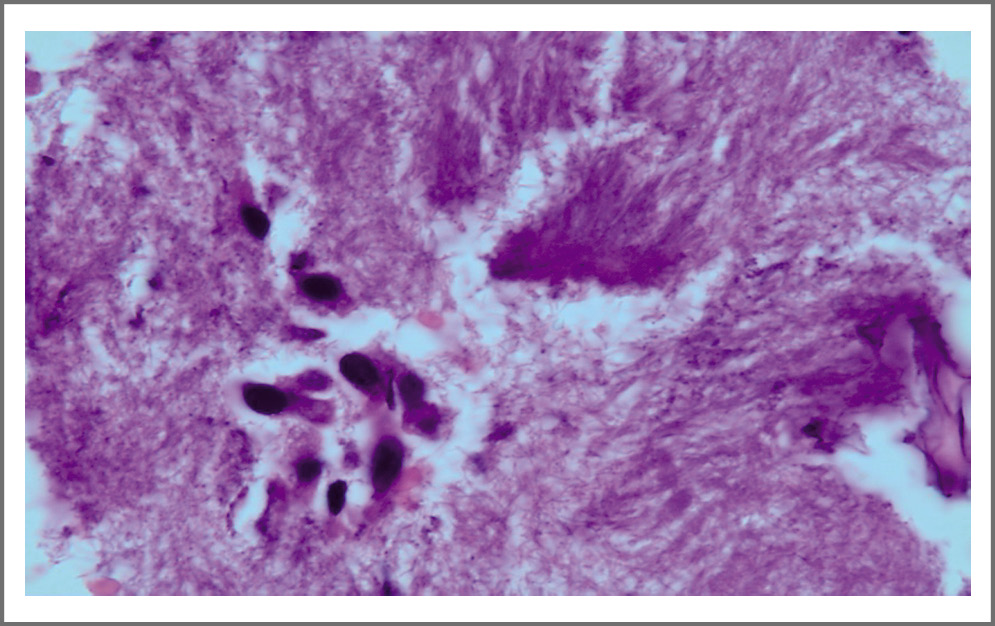

16.06.2020 амбулаторно в условиях наркоза пациенту выполнено бронхологическое обследование и выявлен компрессионный синдром в зоне бифуркации трахеи, правого главного бронха, правого промежуточного бронха. Эндоскопическая картина отражала стеноз 3-й степени промежуточного бронха, экспираторный стеноз трахеи и главных бронхов до 3-й степени. Для уточнения природы выявленных изменений выполнен бронхоальвеолярный лаваж, жидкость которого направлена на цитологическое и микробиологическое исследования. Материалы трансбронхиальной биопсии легкого в зоне компрессии, биопсия бронха, пункционная биопсия ВГЛУ, прилежащего к промежуточному бронху справа, направлены в лаборатории ФГБНУ ЦНИИТ на морфологическое исследование. При гистологическом исследовании биоптата выявлена картина выраженного хронического с обострением воспаления стенки бронха без признаков специфичности. Кроме того, в препаратах материала бронха и легочной ткани выявлены структуры, подозрительные на принадлежность к нитям мицелия (рис. 2).

Рис. 2. Гистологический препарат. Бронхобиопсия. Нитевидные мицеллярные структуры среди клеток эпителия слизистой стенки бронха. Окраска гематоксилином и эозином. ×1000.

Fig. 2. Histological specimen. Bronchobiopsy. Filamentary myciliary structures among epithelial cells of the bronchial mucosa. Staining with hematoxylin and eosin. ×1000.

Для уточнения диагноза гистологические препараты были консультированы в Инфекционной клинической больнице №2, где диагноз грибкового поражения стенки бронха был подтвержден.